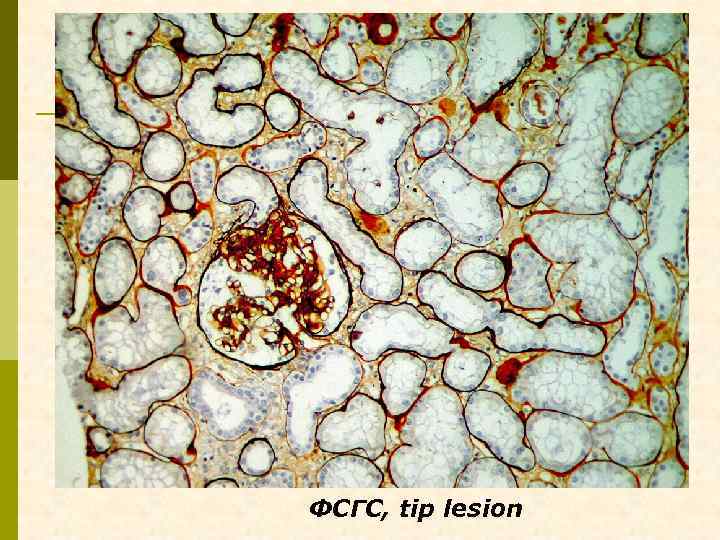

А. Клинический случай № 22041 Ольга Г. , 1971 г. рожд. , в конце марта 1997 г. появились отеки на ногах, которые медленно нарастали. В апреле 1997 г. при обследовании в ЛОКБ определен Мез. ПГН, в течение полугода лечилась преднизолоном, затем в течение 6 лет не наблюдалась. Рецидив нефротического синдрома в 2003 г. После повторного курса преднизолона – практически полная ремиссия, предполагали липоидный нефроз. В марте 2004 г. – анасарка, преднизолон, ремиссия НС. 2006 г. – рецидив отеков, обнаружены гепатит С и ВИЧ. Отсутствие эфффекта от преднизолона, сепсис. Повторная диагностическая нефробиопсия.

ФСГС, tip lesion

4 случая ВИЧ – 4 варианта морфологических феноменов ВИЧ-ассоциированной нефропатии p А – ФСГС, tip lesion p Б – МПГН криоглобулинемический p В – мембранозная нефропатия + ФСГС коллаптоподобный p Г – Ig. A нефропатия